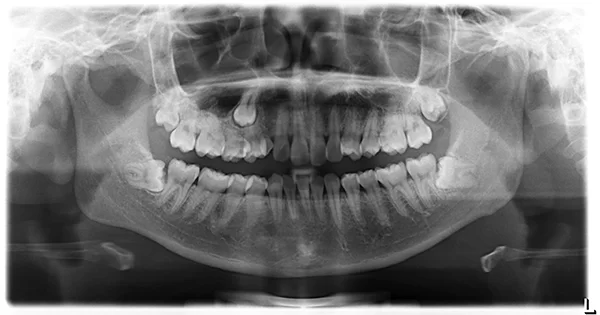

![]() Phim panorex được chụp tại TT Nha Khoa DrHùng & CS (Nam 23 tuổi – cần nhổ 4 răng khôn) |

Chú thích hình: A – B. Răng khôn mọc lệch xa C. Răng khôn lệch gần D. Răng khôn mọc ngầm |